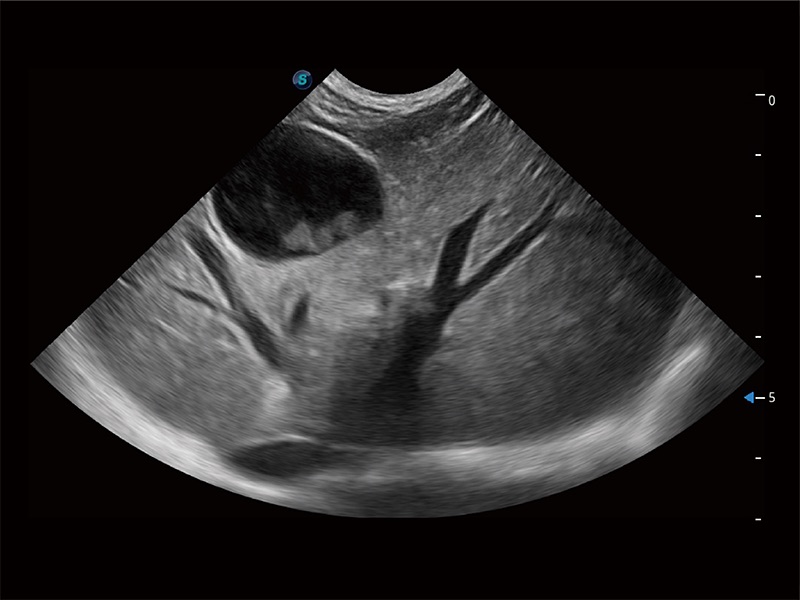

优异的基础图像

ProPet 80 全新的动物超声智能软件和丰富的探头群,为动物医生提供了高清晰度和精细分辨率的图像,无论在宠物、马科、畜牧还是实验室动物等应用中都可以轻松应对,为您的日常工作带来满意的体验。

(犬)肠道